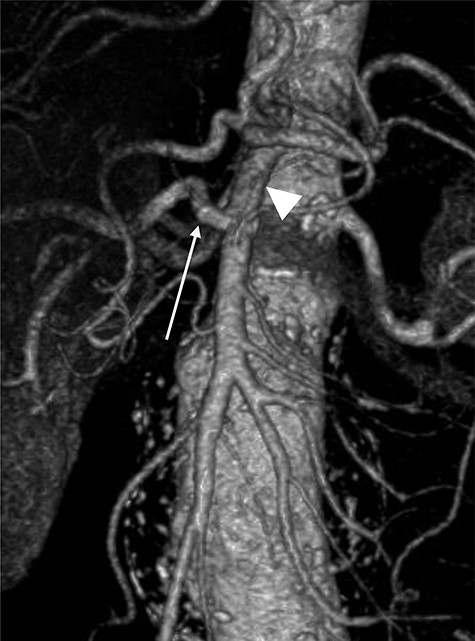

Although this was a planned elective FEVAR, several complications requiring two laparotomies, multi-organ dysfunction as well as patient’s multiple comorbidities contributed to prolonged intensive care unit (ICU) stay and delayed discharge. However, a multidisciplinary approach involving relevant specialties had allowed him to make a good recovery for rehabilitation and discharge home. Surveillance CT aorta at 1 month and 6 months post FEVAR showed satisfactory FEVAR appearance with no endoleak (Fig. 5).

Follow-up CTA showing all visceral stents patent and RRHA (arrow) from SMA (arrowhead).